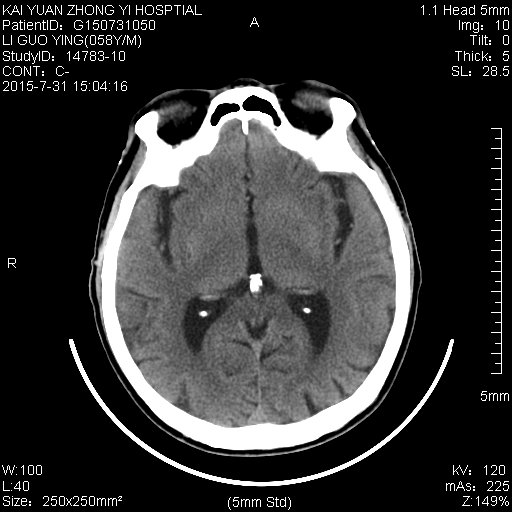

本帖最后由 cefcmj 于 2015-7-31 21:39 编辑 头晕,病变区ct值8Hu 。请各位老师 看看 指教!

1)胼胝体病变,考虑胼胝体变性,梗死待排?请详细了解病史,是否有长期 大量饮酒史?

2)左侧基底节区腔隙性脑梗塞。

3)脑萎缩。

支持1)胼胝体变性。2)双侧基底节区多发性腔隙性脑梗塞。3)脑萎缩。

胼脂体压部变性,考虑酒精中毒性脑病可能

1)胼胝体变性。2)双侧基底节区多发性腔隙性脑梗塞。3)脑萎缩。